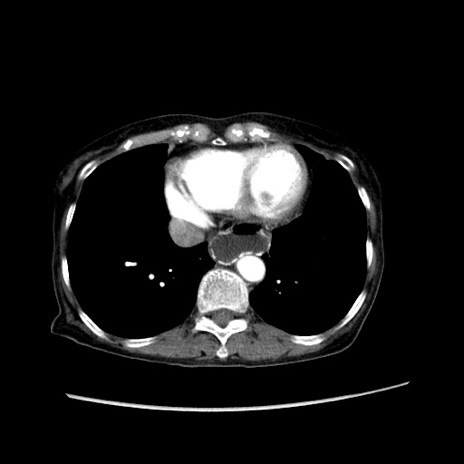

症例25(横断像)

【症例】80歳代女性

【主訴】胸のつかえ感

【現病歴】約9時間前に食後から胸のつかえた感じあり、嘔吐あり、来院。

【既往歴】胃癌(全摘)、胆摘、虫垂炎

【身体所見】心窩部に圧痛あり、反跳痛なし。

【データ】WBC 5700、CRP 0.05